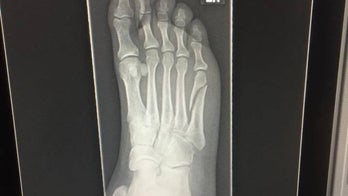

Orthopedics - Page 54